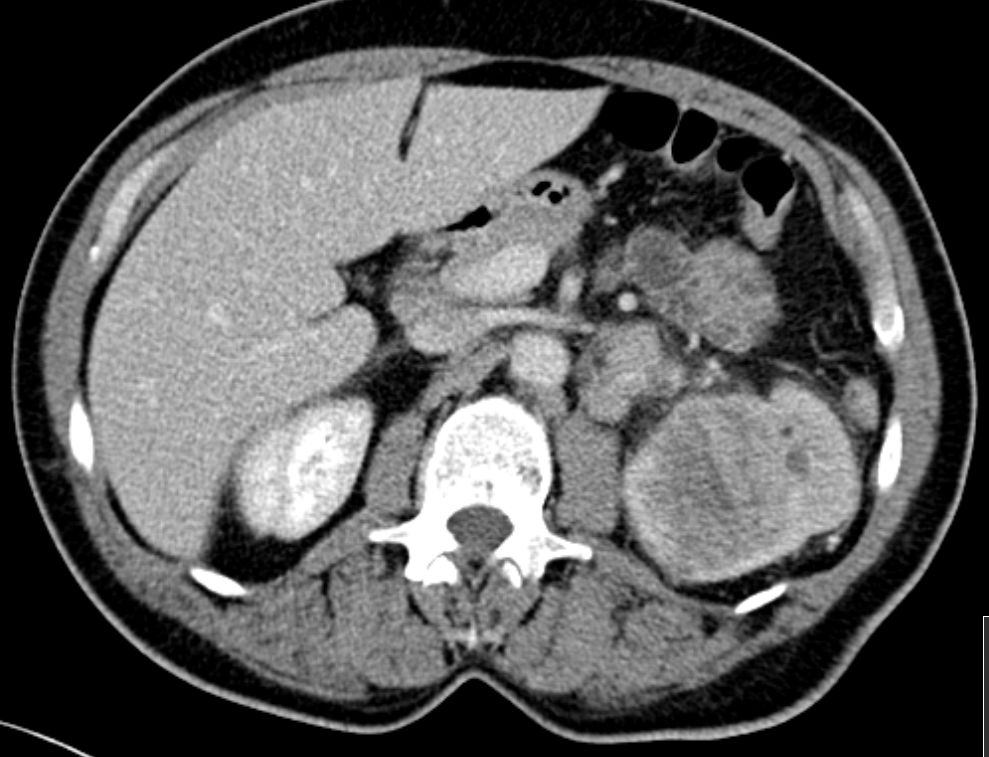

54-jähriger Mann mit

Rückenschmerzen. Bei der Durchuntersuchung wurde eine Metastase in BWK5 mit drohendem Querschnitt gefunden. Es erfolgte eine Laminektomie und Stabilisierung von Pedikelschrauben von T3,4 aud T6,7. Als Primärtumor wurde ein Nierentumor T3 pN2(4/5) m1oss gefunden. |

Histochemie: GATA 3 kräftige Kernfärbung. Zytokeratin 7, Zytokeratin färben Tumorzellen kräftig zytoplasmatisch.Zytokeratin 5/6 negativ. p40 färben einen Teil der Tumorzellkerne. Diagnose: invasives Urothelkarzinom des Nierenbeckens mit Lymphknotenmetastasen. | ||